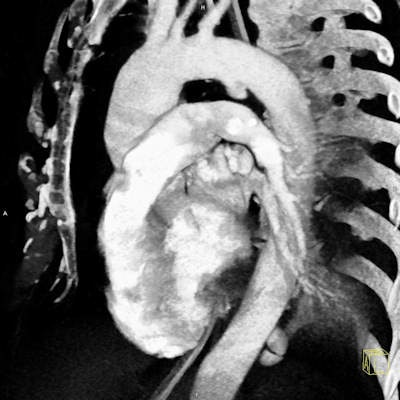

The great strength of multidetector-row CT (MDCT) is its high speed and high geometric resolution in any plane, noted Dr. Hynek Mirka, PhD, deputy head of research and development in the department of imaging methods at Charles University and University Hospital in Pilsen, Czech Republic. It makes it possible to view large parts of the body with minimal motion artifacts and to create accurate multiplanar and 3D reformations, which boosts the accuracy of the diagnosis significantly. Because of these advantages, MDCT has become the first-choice method in high-energy traumas.

In the article, Mirka and colleagues summarize the position of MDCT in the diagnostic algorithm of chest injuries, technical aspects of the examination, and imaging findings in traumas of the individual chest compartments. They explain how detailed information can be acquired in a short acquisition time, and multiplanar and 3D reformatting make the diagnosis significantly more accurate.

Injury to the lung parenchyma includes pulmonary contusion, laceration, torsion, and herniation. These conditions can be complicated by atelectasis, aspiration pneumonia, or acute respiratory distress syndrome. Lung trauma is seldom a reason for surgical treatment, according to the authors. This is indicated in cases of injury of the major blood vessels, signs of active bleeding, large hematomas, or hemodynamic instability in the context of pulmonary involvement.